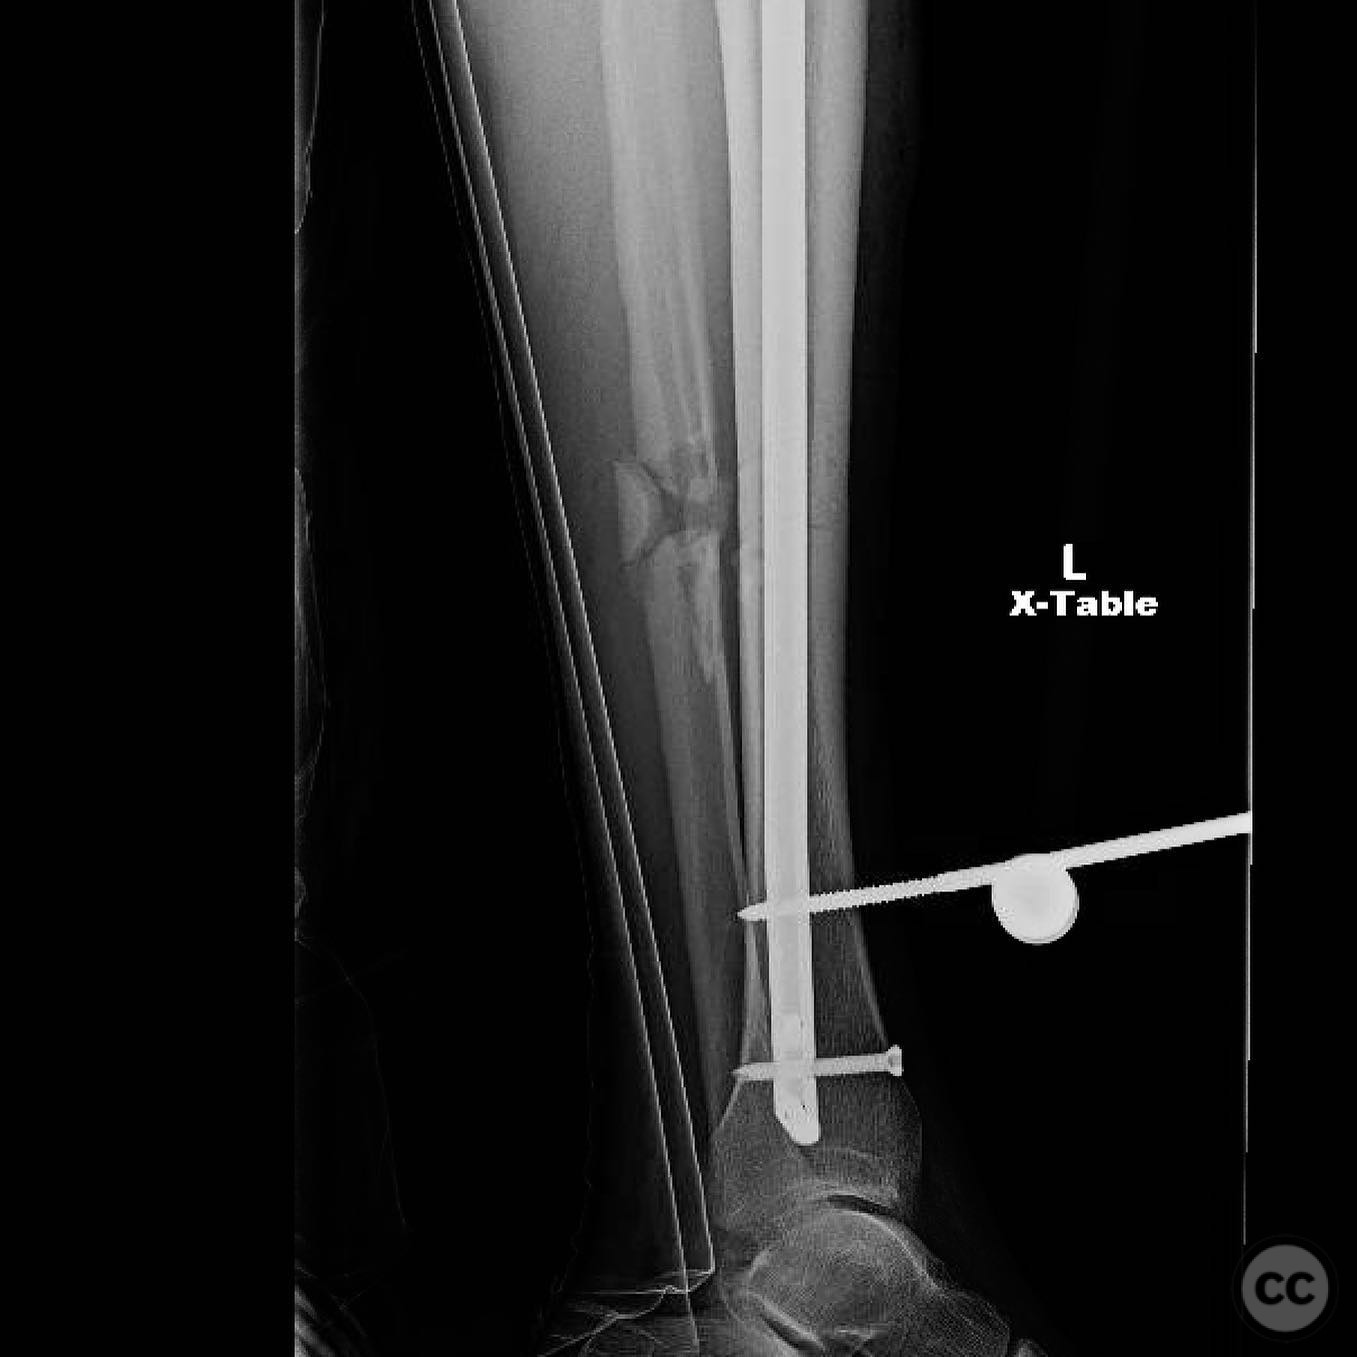

Clinical and radiological findings:  A 44-year-old male cyclist was involved in a collision with a car, resulting in open fractures of the distal femur and segmental tibia. The femoral fracture presented with a 4 cm transverse wound on the anterior aspect, while the tibial fracture had a 2 cm anterolateral wound at the distal site. There were no associated head, chest, or abdominal injuries, and compartment syndrome was not present. Vascular examination was unremarkable.

Planning remarks:  The preoperative plan involved initial debridement and irrigation of both open fractures. The tibia was prioritized for intramedullary nailing, followed by spanning external fixation of the distal femur. Definitive fixation of the distal femur was planned for two days post-initial stabilization.

Anatomical surgical approach:  For the tibia, a longitudinal incision was made to access the proximal tibial start site for intramedullary nailing. Percutaneous clamps were utilized for reduction, supplemented by blocking screws as needed. For the distal femur, an external fixator was applied initially, followed by an in situ lateral approach for plating after reduction was achieved.

Orthopaedic implants used:   Intramedullary nail for tibia, external fixator for initial femoral stabilization, and locking plate for definitive femoral fixation.